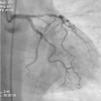

Transferido para este hospital por síndrome coronária aguda (SCA) com elevação do segmento ST da parede anterior extenso com 4 horas de evolução para angioplastia direta. A coronariografia mostrou doença coronária de três vasos associando: estenoses suboclusivas do segmento proximal (lesão culprit) e distal da descendente anterior (DA), estenose crítica do segmento médio da DA, estenoses significativas da coronária direita (CD) e da circunflexa (Cx). Submetido a intervenção na DA com implantação de três stents metálicos e bom resultado final. Durante o internamento permaneceu sem recorrência de angor, mantendo estabilidade elétrica, hemodinâmica e classe de Killip 1. Evoluiu com ondas Q associado a supradesnivelamento de ST e inversão da onda T de V1-V4, pico de troponina I > 100 ng/ml, Ckmassa 105,6 ng/ml e BNP máximo de 2.490 pg/ml.

Transferido para o Hospital de origem com o diagnostico de enfarte agudo do miocárdio (EAM) precipitado pelo uso de zolmitriptano (Figuras 1–5).